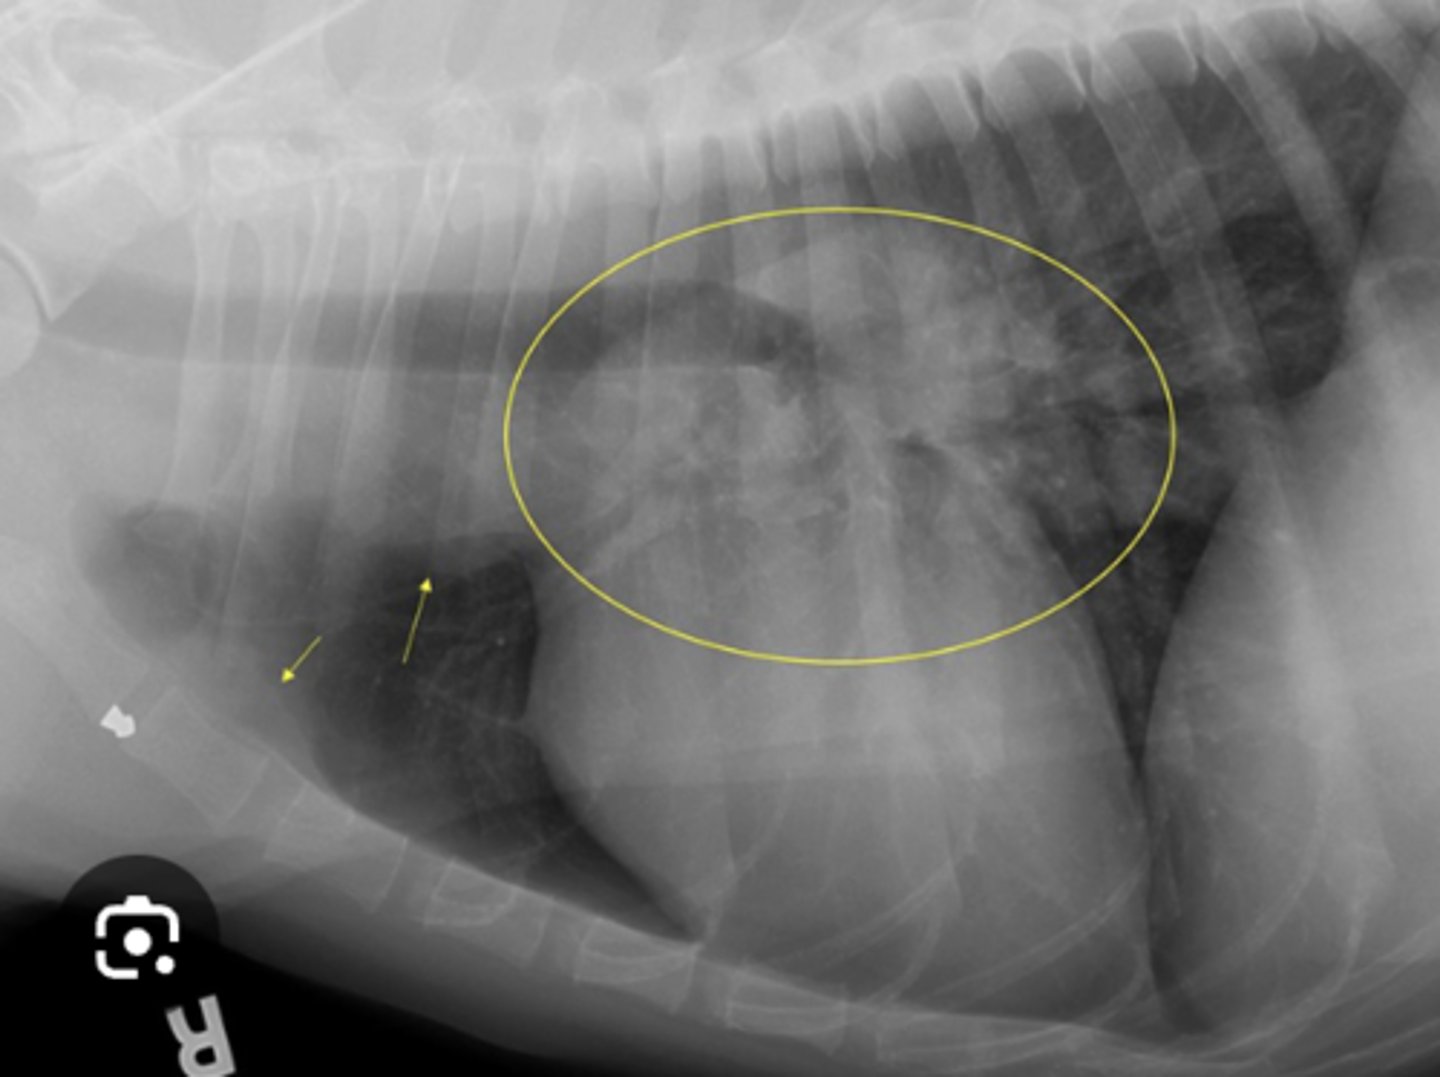

Use this image with this question "Rocky', a 4-year-old Gordon Setter, is presented with a rapid onset of dyspnea. Lung sounds are decreased. The owner is not much help but says "Rocky' was fine yesterday. Only one radiographic view is available, because the patient is distressed. What is your diagnosis based on this lateral radiograph?

Pleural effusion